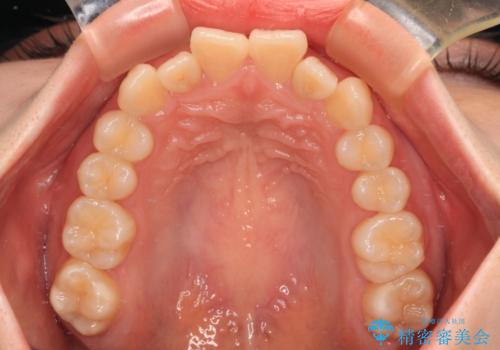

飛び出した前歯を引っ込める ワイヤー装置の非抜歯矯正

- 上下前歯のデコボコを気にして来院された患者様です。

マウスピースでもワイヤー装置でも対応可能でしたが、右側の咬み合わせが上顎がやや前方に位置していることから、補助装置を使用することが推奨されました。

右上と左下の第一大臼歯2本が周辺の歯と比べて位置がずれていたため、ゴムかけやワイヤーに曲げを入れることで移動を試みましたが、どうよら癒着をしており、移動困難と判断されました。